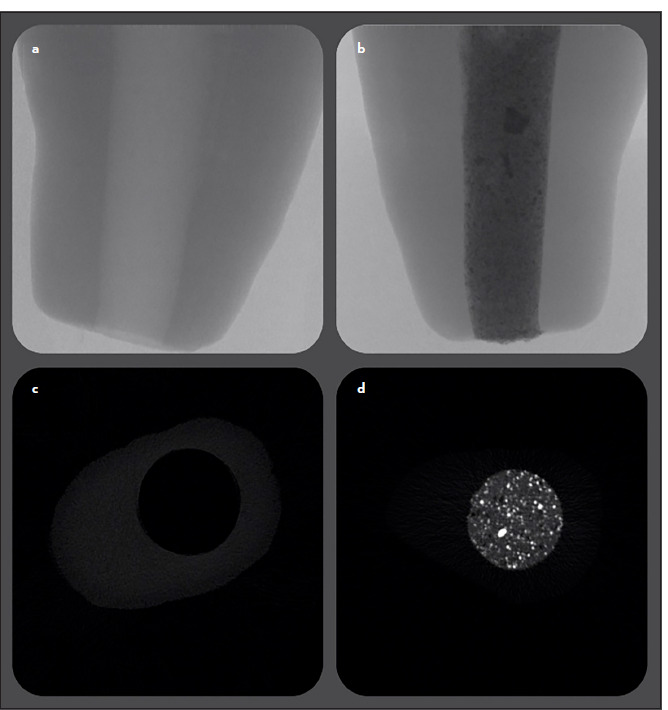

Methods: Thirty-six freshly extracted single-rooted teeth with straight root canals were used, divided into three groups based on the materials. Immature teeth were simulated. Pre- and post-obturated micro-CT images were taken for each root. Voids were calculated as the percentage difference between canal space volume and repair material volume. The data were then analysed statistically using one-way analysis of variance (ANOVA) with the level of significance set at α=0.05.

Results: All groups showed marginal gaps and/or internal voids after root-end filling. No significant difference between groups in canal and material volumes was detected at 3 mm (p>0.05). However, void percentage differences were significant (p=0.003); Bio-C Repair (9.28+-3.27%) and EndoSequence BC RRM (6.7+-2.72%) were significantly higher with no difference between them, while NeoMTA Putty (3.73+-1.69%) was significantly lower.